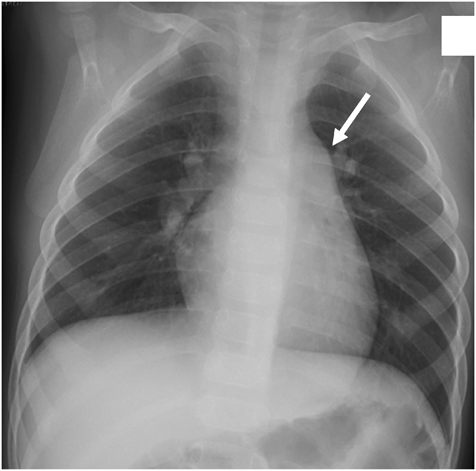

Chest radiography showed no abnormalities in the lung field and no cardiac enlargement. The main pulmonary artery was slightly enlarged (Fig. 1). Electrocardiography (ECG) showed a sinus rhythm with right axis deviation (Fig. 2). Echocardiography revealed enlargement of the right ventricle (RV) and right atrium (RA) and bulging of the interventricular septum to the left ventricle (LV). Tricuspid regurgitation (TR) was moderate, with a peak TR jet velocity of 4.29 m/s (Fig. 3). RV pressure was estimated to be 73 mmHg plus RA pressure; accordingly, severe PAH was suspected. Contrast echocardiography was performed to differentiate diseases causing hypoxemia. Microbubbles were stagnant in the RA and RV, with RV function markedly deteriorated, and did not enter into the left heart. A sildenafil (1 mg/kg) administration test was carried out through a nasogastric tube under oxygen administration using a high flow nasal cannula. One hour later, echocardiography showed that the abnormal arrangement of the interventricular septum had become normally round, that TR had improved to mild, and that the peak TR jet velocity had attenuated to 2.89 m/s (Fig. 4). Tachycardia and tachypnea disappeared, and blood pressure came up. Based on his dietary history, thiamine (30 mg) was injected intravenously followed by oral thiamine (25 mg/day) continued for possible cardiovascular beriberi due to vitamin B1 deficiency. Since idiopathic PAH could not be ruled out entirely, tadalafil (1 mg/kg/day) was started from the day of admission. TR eventually disappeared on echocardiography on the same day. The RV and the RA gradually became smaller.

Fig. 1 Chest radiography showed no abnormal shadow in the right or the left lungs. Cardio-thoracic ratio 49%. The main pulmonary artery was slightly enlarged (white arrow)